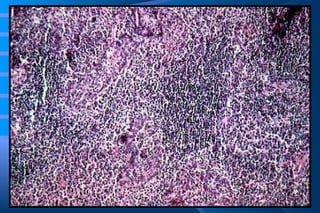

Amyloidosis of the kidney. The glomerular architecture is almost totally obliterated by the massive accumulation of amyloid

Amyloidosis - Morphology ◘  Kidney - most common and potentially the most serious form of organ  involvement - may appear normal in size and color or it may be enlarged in  advanced cases - it may be shrunken and contracted due to vascular  narrowing induced by amyloid deposits - deposited primarily in glomeruli, but also affected  are the  interstitial peritubular tissue, arteries, and  arterioles

Amyloidosis - Morphology ◘  Kidney    thickening of the mesangial matrix + uneven widening of the basement membrane of glomerular capillaries    capillary narrowing and distortion of glomerular vascular tuft    obliteration of capillary lumens    masses or interlacing broad ribbons of amyloid